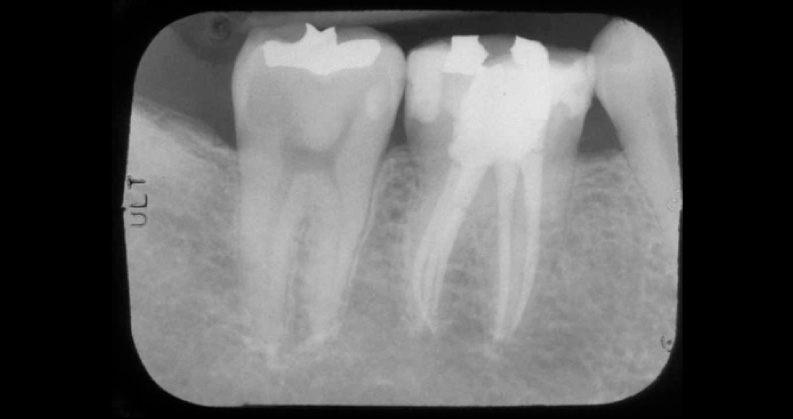

Estudos mostram que o simples acesso endodôntico não é capaz de fragilizar a estrutura dentaria em mais do que 5%. Na verdade, o que leva o dente à fragilidade é a perda da estrutura dental causada pela extensão de tecido cariado e/ou pelo tamanho de fratura coronária.

Enfim, é a situação clínica como um todo que torna esse dente mais frágil e não o tratamento endodôntico por si só.

Por isso é muito importante que, após o canal finalizado, seja feita a escolha correta do material restaurador, seja ele uma restauração direta ou indireta. (com pinos, coroas metalo-cerâmicas, onlays).

Assim, restabelecendo a resistência da estrutura dental e voltando à atividade mastigatória sem risco de fratura do dente. Essa, que muitas vezes, pode se estender à raiz, levando à perda do dente.